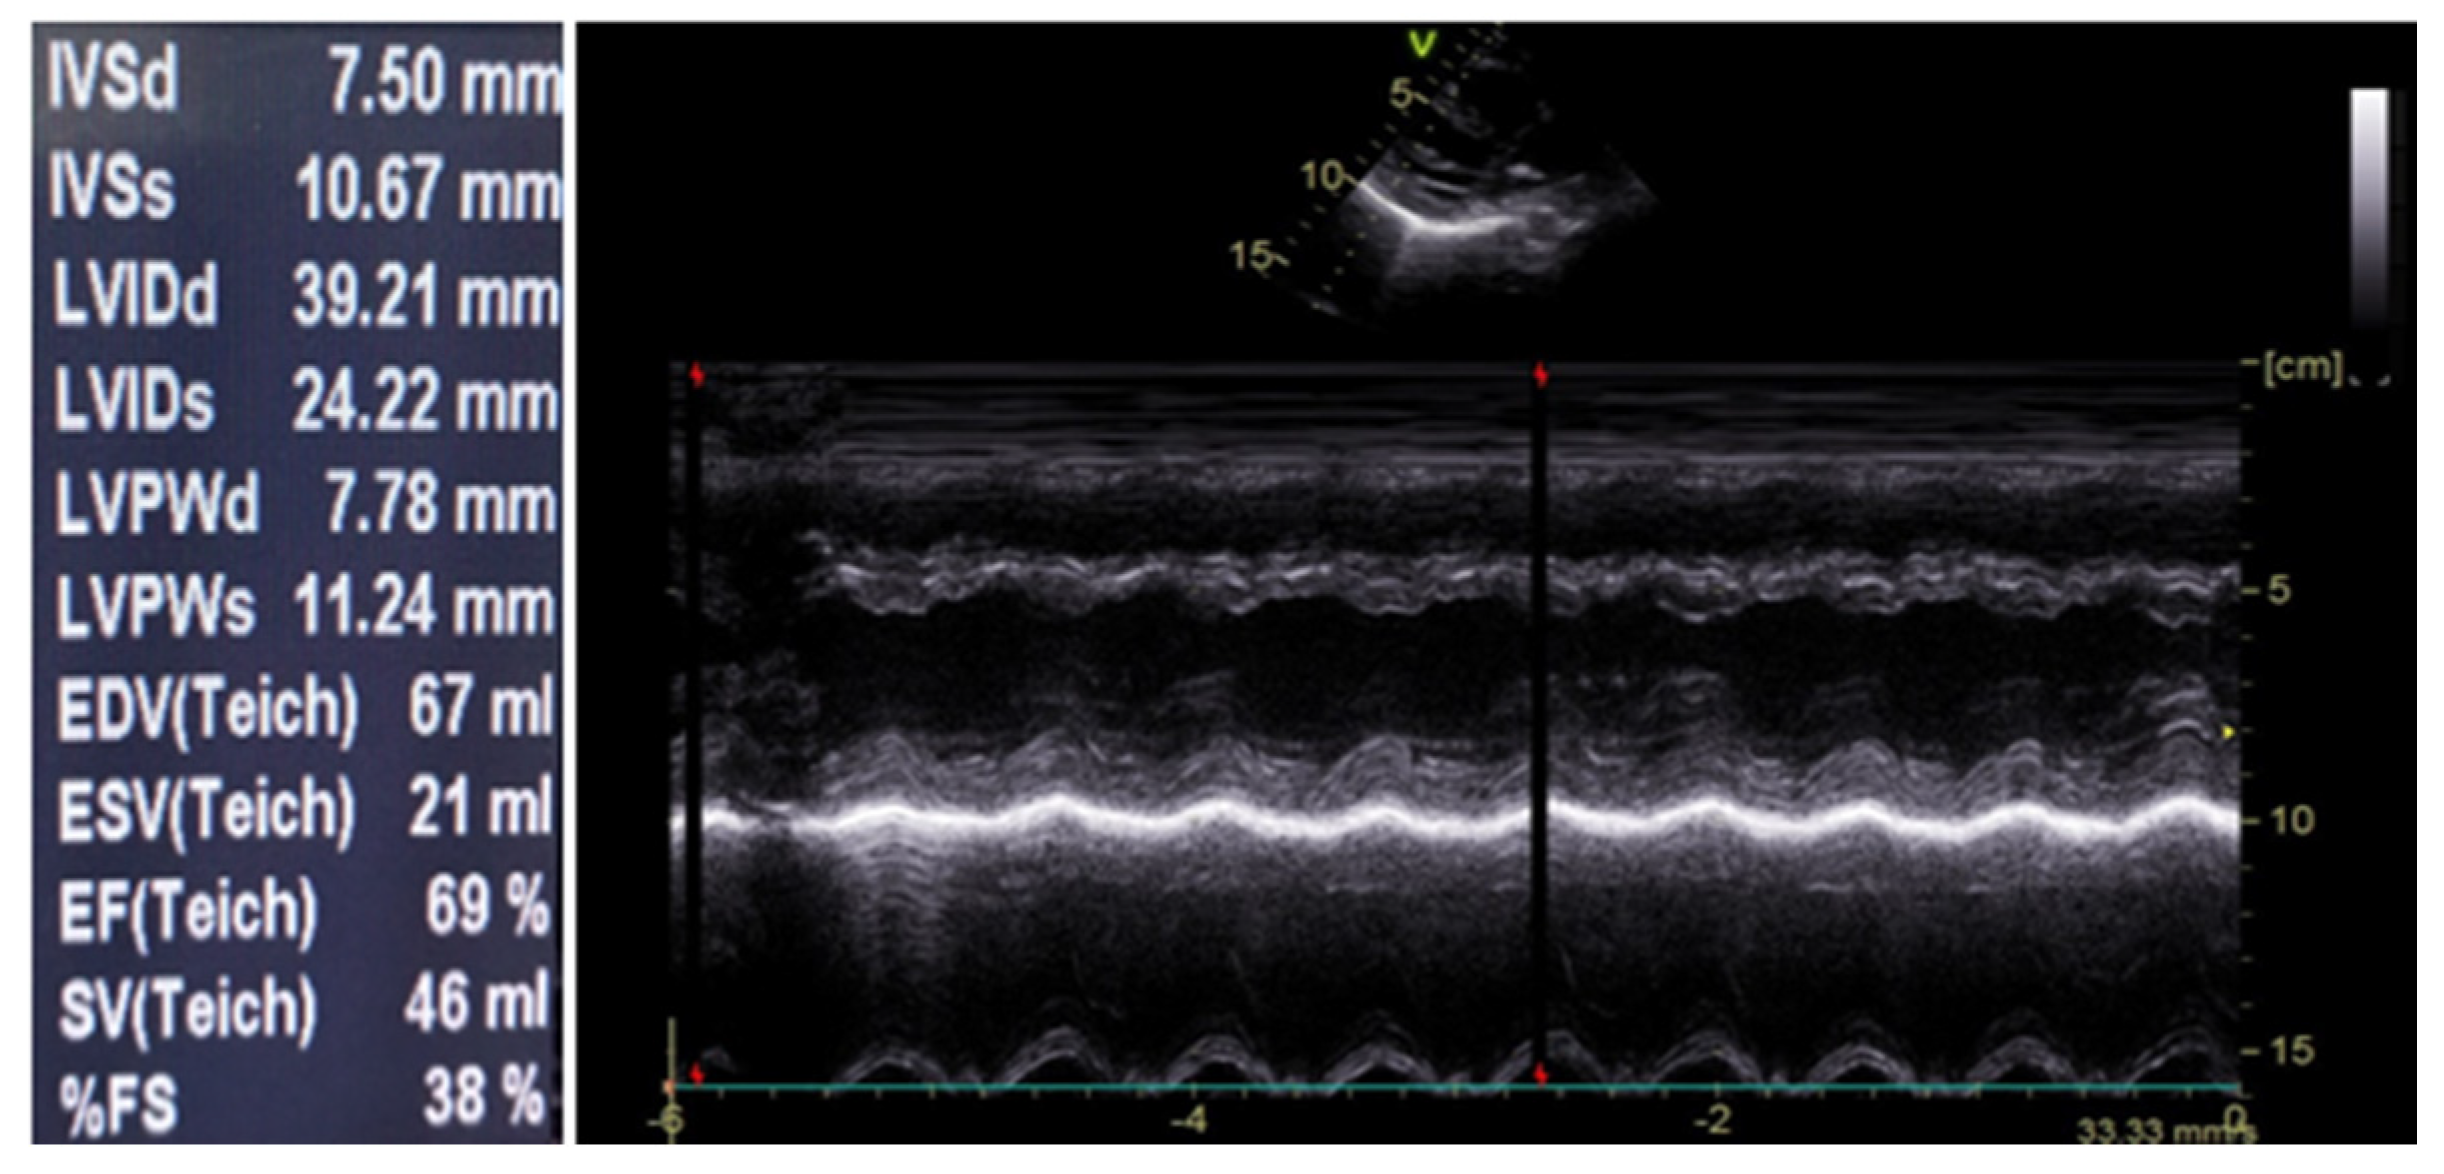

Upon admission, the patient received intravenous maintenance fluids and remained in good general condition. During the second day of hospitalization, she had three episodes of fever (Tmax = 38.2 °C) and started to complain about stabbing, intermittent pain at the anterior chest, without radiation. There were no alleviating or aggravating factors. Her physical examination was unremarkable. Laboratory investigation including cardiac biomarkers were sent and showed elevated total Creatine Kinase (CK) (307 IU/L; reference range <140), CK-MB (25.3 ng/mL; reference <3), and Τroponin-T (456.4 pg/mL; reference< 14) levels (Table 1). An electrocardiogram (ECG) was performed that showed sinus rhythm, normal ST-segments, and normal T waves (Figure 1). Due to persisting chest pain and due to the abnormal cardiac biomarkers, a cardiological consultation was requested. Cardiac echocardiography was performed that showed normal left ventricular (LV) function, with a >65% ejection fraction and no pericardial effusion (Figure 2).

Figure 2.

Cardiac echocardiography on Day 2.